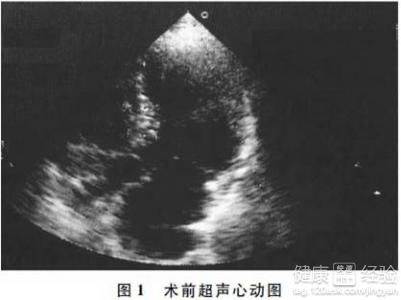

肥厚型梗阻性心肌病的治療方法有哪些?